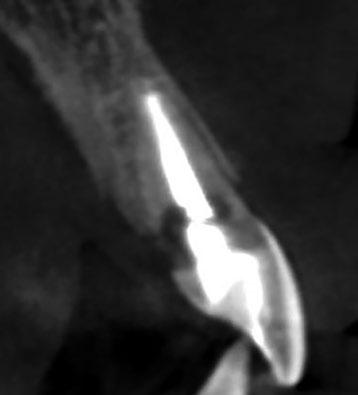

se aprecia una extensa reabsorción radicular interna, con el consiguiente defecto óseo, que se confirma con un CBCT (Fig. 3, 4, 5). Se informa a la paciente del riesgo de fractura espontanea. Esta solicita solucionar el problema antes de que avance más.

En la exploración radiográfica en 3D (CBCT) se aprecia ausencia de cortical vestibular en 2.1 y un defecto óseo horizontal en 1.1 (Figura 3).